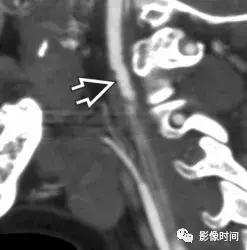

6.纤维肌性发育不良:颈动脉纤维肌性发育不良是一种罕见且无症状的疾病,因此往往是偶然发现的。然而,有症状的病人可以出现脑梗死、短暂缺血、或蛛网膜下腔出血。虽然纤维肌性发育不良可发生在三层动脉壁中的任何一层,但中膜受累是最常见的表现。超过 90% 的病例动脉壁由于纤维增厚和弹性层的破坏而而导致多灶性狭窄和扩张。值得注意的是管腔扩张往往大于正常血管直径,从而有助于区分纤维肌性发育不良和动脉粥样硬化。「串珠」外观在 80% -90% 的病例中都能看到。CTA 和 MRA 是首选检查。

模式图显示纤维肌性发育不良的主要亚型:1 型表现为收缩和扩张的交替;2 型表现为管状狭窄,3 型表现为局灶性波纹+憩室。MRA 显示双侧颈内动脉「串珠」外观(箭头)。CTA 和 DSA 亦显示颈内动脉「串珠」外观。